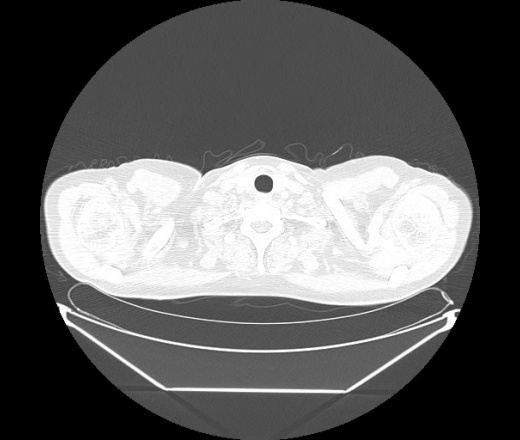

М. 1984 г.р.  Лихорадка 39, кашель , одышка.. и надоевший всем вопрос- "типично ли для ковид?" ( в настоящее время на него обязательно нужно дать ответ в своем протоколе)

На мой взгляд нетипично для ковид: много центрально-расположенных поражений, лобарное поражение нижней доли слева. 50/50

Не типичая картина для ковид.

КТ-признаки двусторонней бактериальной пневмонии.

Все верно, здесь абсолютно нетипичная картина, несмотря на матовое стекло с ретикулярными изменениями, но почему-то  посчитали иначе. Кстати,  "малыша" не заметили)?